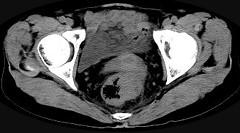

问题 男,56岁,排便形状改变,便不尽感,CT检查如图所示,下列说法正确的是 ( )

选项 A.肠壁上有蒂状新生物 B.其表面光滑,边界清楚 C.肠腔未见狭窄 D.此为直肠息肉 E.此为直肠癌

答案 E